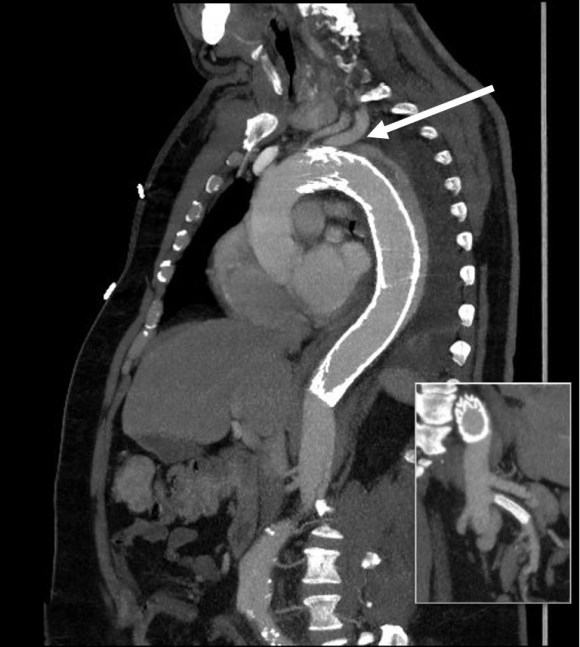

CTA shows the left subclavian artery to be occluded at its origin.

The operation went well. The patient’s angina resolved and a followup CT showed the patent bypass feeding the LIMA and LAD.

At its heart, it would be this vascular surgeon’s attempt at an off-pump single vessel CABG (above). Preparations were made with cardiac anesthesia and cardiac surgery to place an IABP (intra-aortic balloon pump) if he became unstable. For my part, the operation was straightforward, but I was going to have to go about it efficiently. I also figured that with a clamp beyond the LIMA takeoff, no significant change would occur to the coronary flow from the LIMA graft. So I hoped as I worked very deliberately. We kept him on the hypertensive side during the case.